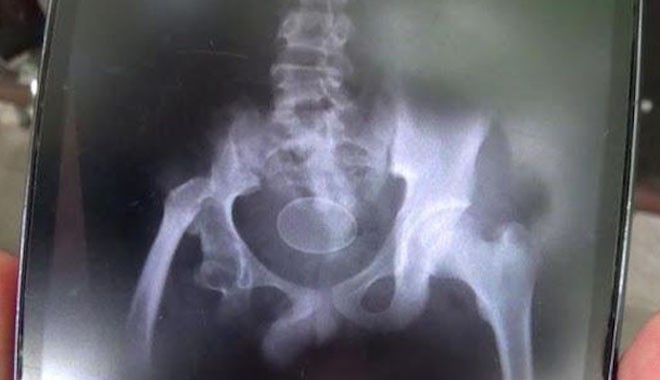

കൂടുതൽ പറഞ്ഞപ്പോൾ സംശയം തോന്നിയ ഡോക്ടർമാർ കുട്ടിയെ എക്സ്റേക്ക് വിധേയമാക്കിയപ്പോൾ ശരിക്കും ഞെട്ടുകയായിരുന്നു. കുട്ടിയുടെ മലാശയത്തിനുള്ളില്‍ ഒരു മുട്ട. പക്ഷെ ഈ കാര്യം ഡോക്ടർമാർ യാതൊരു വിധേനയും അംഗീകരിക്കാൻ തയ്യാറായില്ല. കുട്ടി മുട്ട വിഴുങ്ങിയതോ, മലദ്വാരത്തിൽ കയറ്റി വച്ചതോ ആകാമെന്നാണ് ഡോക്ടർമാരുടെ വാദം.